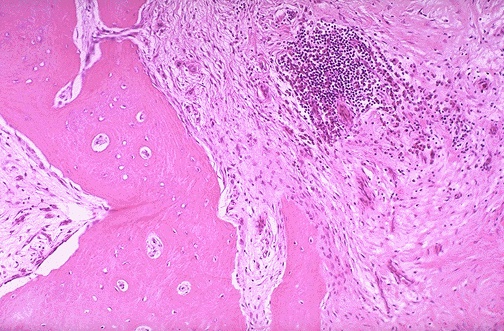

Структура грубоволокнистой костной ткани: наглядные примеры